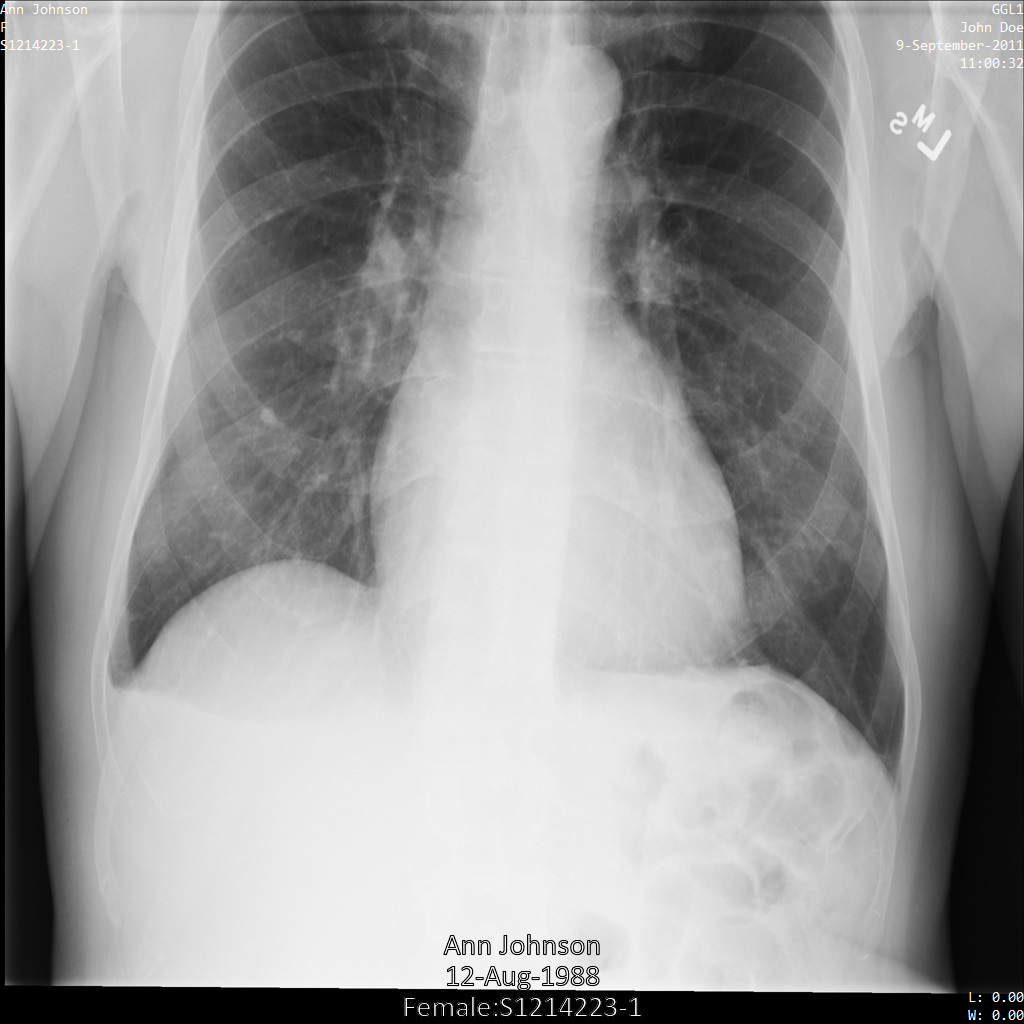

En cada una de las siguientes secciones, se proporcionan ejemplos de cómo desidentificar datos de DICOM mediante varios métodos. Se proporciona un resultado de la imagen desidentificada en cada muestra. En cada muestra, se usa la siguiente imagen original como su entrada:

Puedes comparar la imagen de salida de cada operación de desidentificación con esta imagen original para ver los efectos de la operación.

Después de enviar la imagen a la API de Cloud Healthcare mediante el perfil de filtro de etiqueta ATTRIBUTE_CONFIDENTIALITY_BASIC_PROFILE, la imagen aparece de la siguiente manera. Mientras se ocultan los metadatos que se muestran en las esquinas superiores de la imagen, permanece la PHI quemada que se encuentra en la parte inferior de la imagen.

Para quitar también el texto grabado, consulta Cómo ocultar el texto grabado de las imágenes.